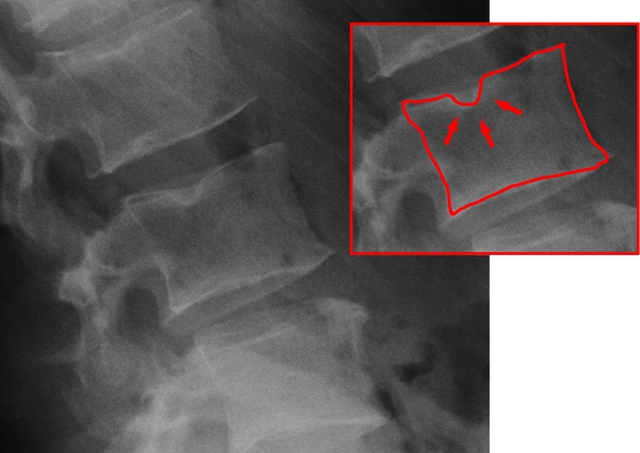

Изображение: J. Lengerke 22:47, 12. Jan. 2010 (CET), CC BY-SA 3.0, via Wikimedia Commons

Изображение: Marcello Henrique Nogueira-Barbosa, Michel Daoud Crema, Carlos Fernando Pereira da Silva Herrero, Wagner Pasqualini, Helton Luiz Aparecido Defino, CC BY 4.0, via Wikimedia Commons

Диагноза

Диагностицирането на телцата на Шморл се извършва чрез снемане на анамнеза, физикален преглед и чрез образни изследвания на гръбначния стълб, които обикновено изобразяват областта на долната част на гърба. Може да се приложат:

Обикновено чрез образните методи се установява дефект в крайната пластинка и херниирал дисков материал в тялото на прешлена